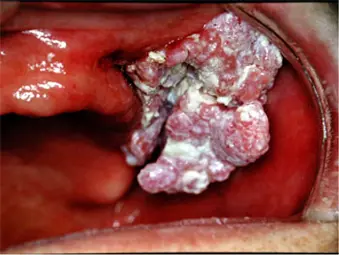

このような方は受診してください〜前がん病変と呼ばれています

- 白板症(はくばんしょう)

- 紅板症(こうばんしょう)